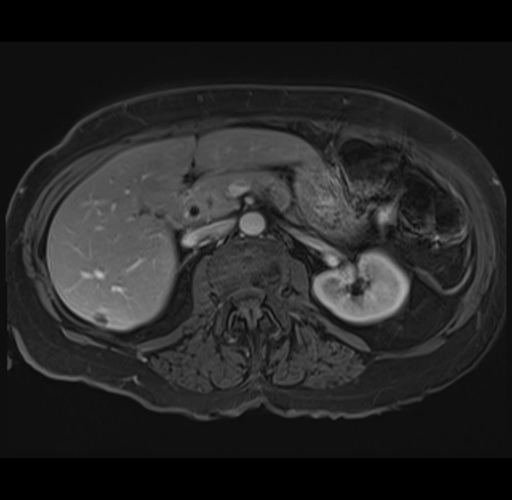

MRI T1

Imaging analysis